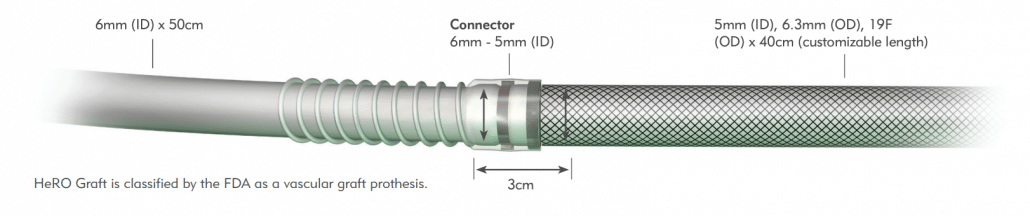

HeRO Graft (Hemodialysis Reliable Outflow) is the ONLY fully subcutaneous AV access solution clinically proven to maintain long-term access for hemodialysis patients with central venous stenosis. HeRO Graft is classified by the FDA as a graft, but differs from a conventional AV graft since it has no venous anastomosis. It consists of two primary components:

The HeRO Graft Arterial Graft Component has a 6mm inner diameter (ID), 7.4mm outer diameter (OD), and is 53cm long, inclusive of the connector. It consists of an ePTFE hemodialysis graft with PTFE beading to provide kink resistance near the proprietary titanium connector. The titanium connector attaches the Arterial Graft Component to the Venous Outflow Component. The Arterial Graft Component is cannulated using standard technique according to KDOQI guidelines.

The HeRO Graft Venous Outflow Component has a 5mm ID, 19F (6.3mm) OD, and is 40cm long. It consists of radiopaque silicone with braided nitinol reinforcement (for kink and crush resistance) and a radiopaque marker band at the distal tip.